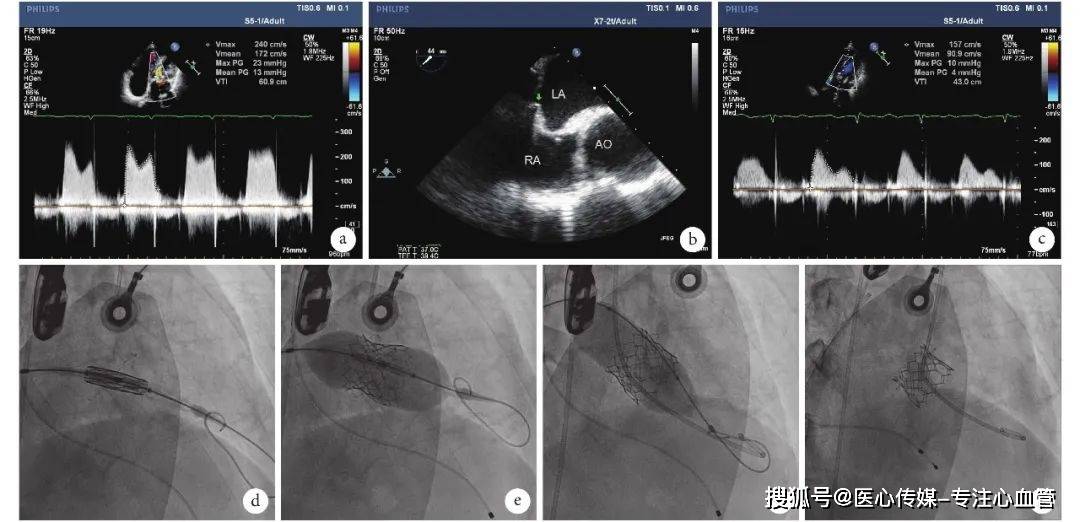

病例报告丨股静脉-房间隔途径经导管二尖瓣置换术一例_mm